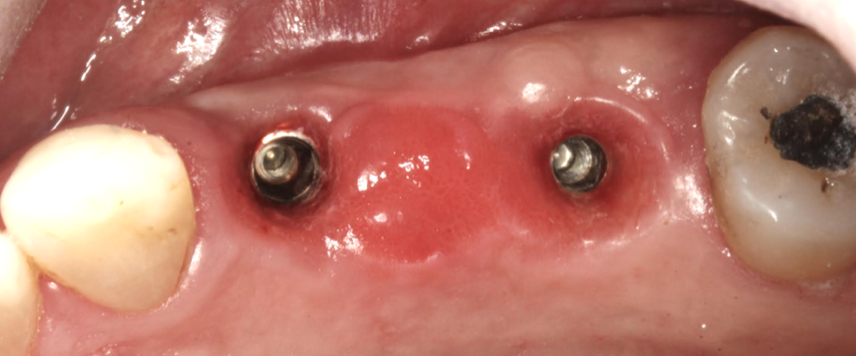

Patient Factors that May Contraindicate Fixed Implant-supported Prosthetics

(42.) Fixed-removable prosthesis.

Figure 42

(43.) Fixed-removable prosthesis.

Figure 43